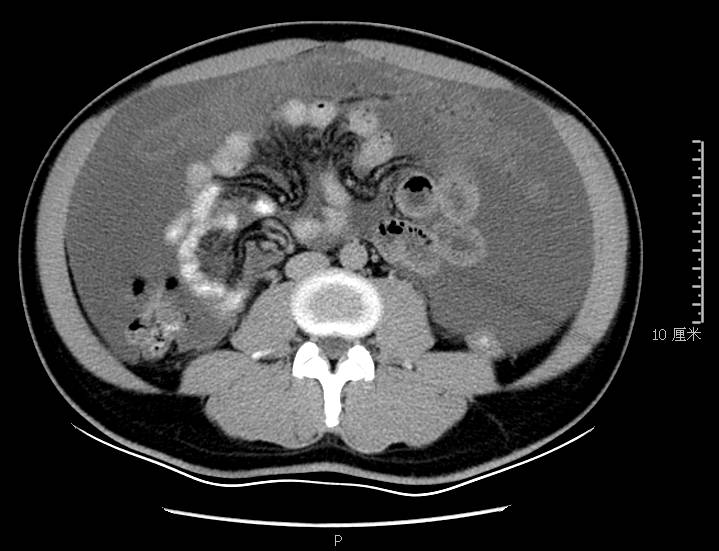

全腹CT:(1)结合病史考虑腹膜炎(见图2A),大量腹水;(2)右骼窝区管状样结构,考虑阑尾扩张(见图2B);(3)肝脏多发小囊肿(见图2C);(4)肝内胆管轻度扩张,建议隔期复查。

图2a大网膜成饼状(CT腹腔横断图象上出现肠曲被前面及两侧的肿瘤组织限制在中央

本例确诊后对B超及CT再次回顾发现:腹腔、盆腔可见不均质中强回声包块,部分呈囊实状,腹膜增厚,大网膜成饼状(如图2A)和肝周可见不均质中强回声弧形压迹、脾周可见不均质中强回声包饶,肝脏成扇贝样改变(如图2C),但在诊断报告中未提及。有学者发现mantle和scalloping(如图2A,2C)在PMP中具有代表性,且mantle较scalloping更为常见,若mantel征同时伴有大小不一的囊性改变,则更具诊断价值。

通过本病例分析认为此类患者,腹穿时若发现腹水不易抽出或抽出物为黏稠胶冻样,腹部B超提示液性暗区内有漂浮的团状回声有分隔,撞击腹部后可出现“礼花”样改变,肝脾包膜完整不光滑,有弧形压迹,全腹部CT示弥散占位,可见mantle和scallping征、大网膜成饼状且阑尾扩张应高度怀疑本病。